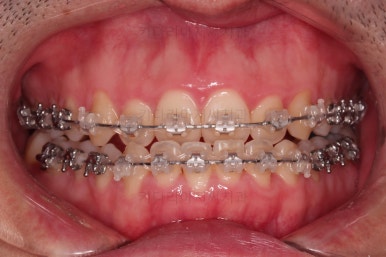

수술 전 교정과정이 거의 마무리 되어 갑니다.

오히려 앞니가 거꾸로 물리는 정도는 더 심해지고요.

수술 직전이 얼굴모습도 가장 주걱턱이 심한 양상으로 됩니다.

농담 삼아 못생겨지면 못생겨질수록 수술이 더 잘될겁니다 라고 말씀 드립니다.